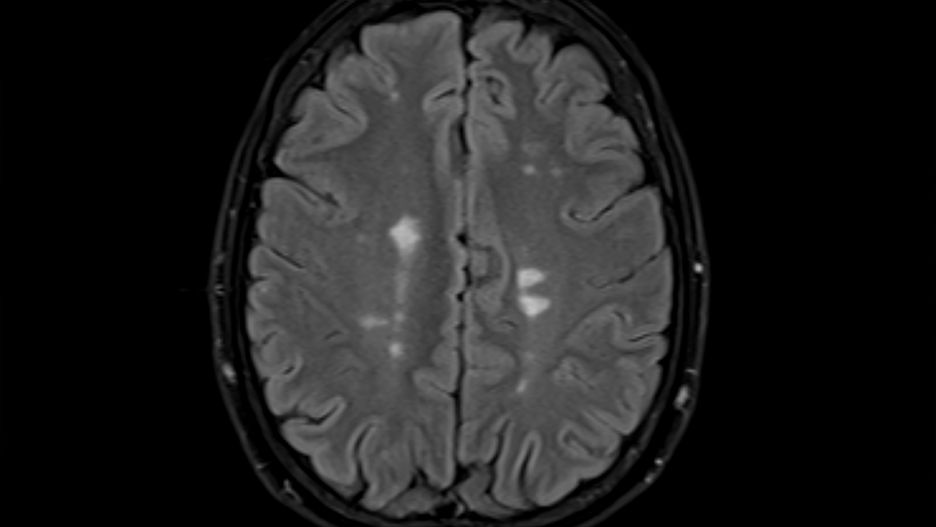

Stwardnienie rozsiane powoduje zmiany w mózgu prowadzące najczęściej do trwałej niepełnosprawnościStwardnienie rozsiane powoduje zmiany w mózgu prowadzące najczęściej do trwałej niepełnosprawności

Źródło zdjęć: © Getty Images | Paul Biris

Stwardnienie rozsiane to choroba ośrodkowego układu nerwowego, w której dochodzi do wieloogniskowego uszkodzenia tkanki nerwowej. Objawy obejmują zaburzenia widzenia, problemy z poruszaniem i czuciem. Choroba ta jest obecnie uznawana za nieuleczalną.